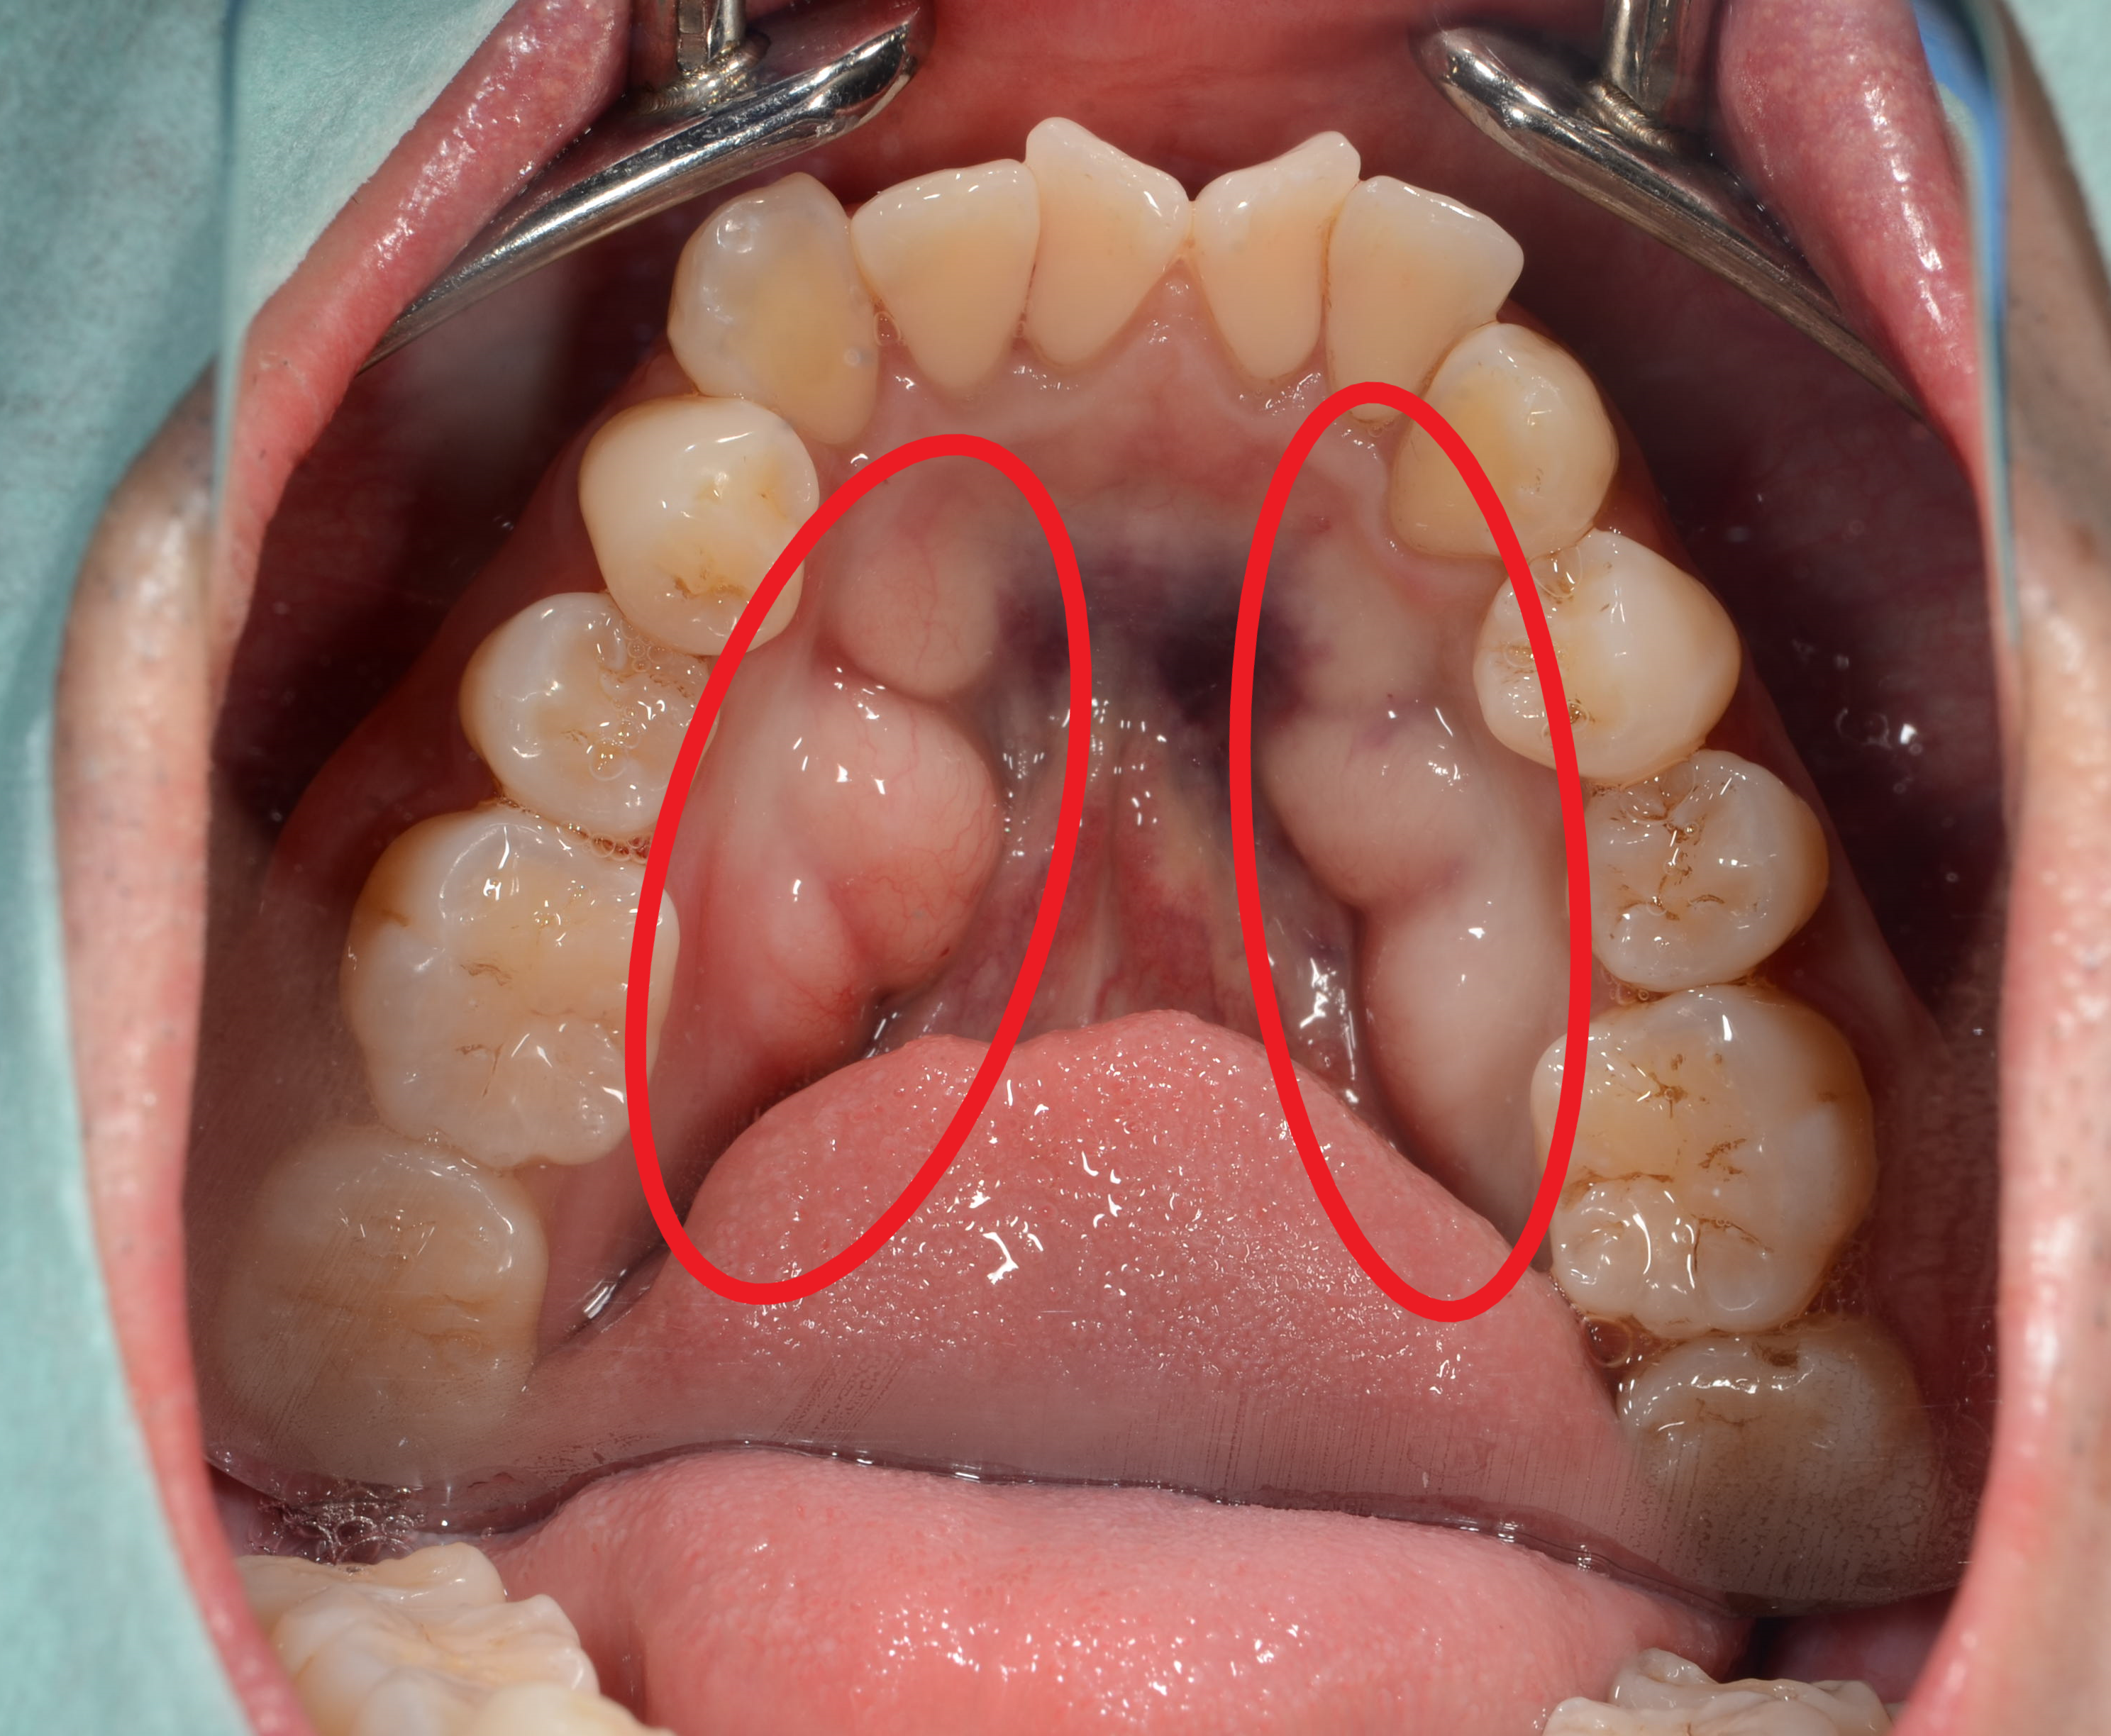

骸骨 歯-根尖性歯周炎は、歯根の尖端部周囲に限局した炎症ですが、進行すると、歯槽骨炎 (しそうこつえん)やさらに広範な顎骨炎などに進展します。 感染の広がりとともに症状も顕著となり、局所の発赤 (ほっせき)や腫脹 (しゅちょう)、疼痛 (とうつう)に加えて、発熱などの全身症状を伴うようになります。 重症例では、感染は顎骨 (がっこつあごの骨)から周囲の口底やSync 頭蓋骨 配色 骸骨 模型 顎関節 歯模型 骨格 分解可能 パーツごとに色分けされているためとても見やすく学校課題や勉強に役立ちます。 頭蓋冠は取り外し式になっている為、内部もしっかり見られま

骨髄炎に対する治療 ~ 骨髄炎に対する治療 顎骨骨髄炎 顎骨骨髄炎とは、口腔内細菌の感染に起因する炎症が顎骨内の骨髄にまで波及することで様々な症状を惹起し、時にとても治療が困難となる疾患です。 健康な方であっても、う蝕(むし歯)が進行すると、歯の神経にまで炎症が波及した 顎骨骨髄炎(がっこつこつずいえん)とは 突然あごの骨に激痛が起きる顎骨骨髄炎。 あごの骨の内部にある「骨髄」と呼ばれる部分が虫歯や歯周病菌によって化膿、炎症を起こすことで起こります。 特に強い痛みになりやすいのは急性の顎骨骨髄炎で、主に感染が下あごに起きた場合に見られます。 普通、あごの骨は歯茎や筋肉などに覆われているため